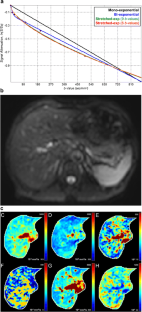

Ninety-five patients underwent DWI using nine b values at 3 T magnetic resonance. The hepatic apparent diffusion coefficient (ADC) from a mono-exponential model, the true diffusion coefficient (D t ), pseudo-diffusion coefficient (D p ) and perfusion fraction (f) from a biexponential model, and the distributed diffusion coefficient (DDC) and intravoxel heterogeneity index (α) from a stretched exponential model were compared with the pathological HF stage. For the stretched exponential model, parameters were also obtained using a dataset of six b values (DDC#, α#). The diagnostic performances of the parameters for HF staging were evaluated with Obuchowski measures and receiver operating characteristics (ROC) analysis. The measurement variability of DWI parameters was evaluated using the coefficient of variation (CoV).

Diagnostic accuracy for HF staging was highest for DDC# (Obuchowski measures, 0.770 ± 0.03), and it was significantly higher than that of ADC (0.597 ± 0.05, p < 0.001), D t (0.575 ± 0.05, p < 0.001) and f (0.669 ± 0.04, p = 0.035). The parameters from stretched exponential DWI and D p showed higher areas under the ROC curve (AUCs) for determining significant fibrosis (≥F2) and cirrhosis (F = 4) than other parameters. However, D p showed significantly higher measurement variability (CoV, 74.6%) than DDC# (16.1%, p < 0.001) and α# (15.1%, p < 0.001).